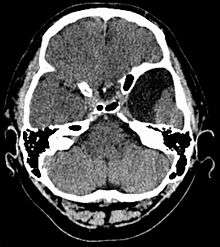

Diagnosis

Diagnosis is principally by MRI. Frequently, arachnoid cysts are incidental findings on MRI scans performed for other clinical reasons. In practice, diagnosis of symptomatic arachnoid cysts requires symptoms to be present, and many with the disorder never develop symptoms.